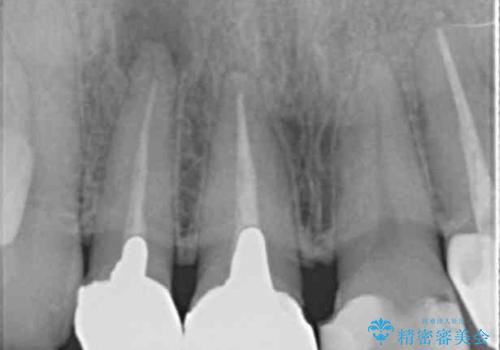

- 前歯を天然の歯のようにきれいにやりかえたいと希望され来院されました。

根尖病変の存在が判明したため、感染根管治療後にオールセラミックジルコニアクラウンを製作します。